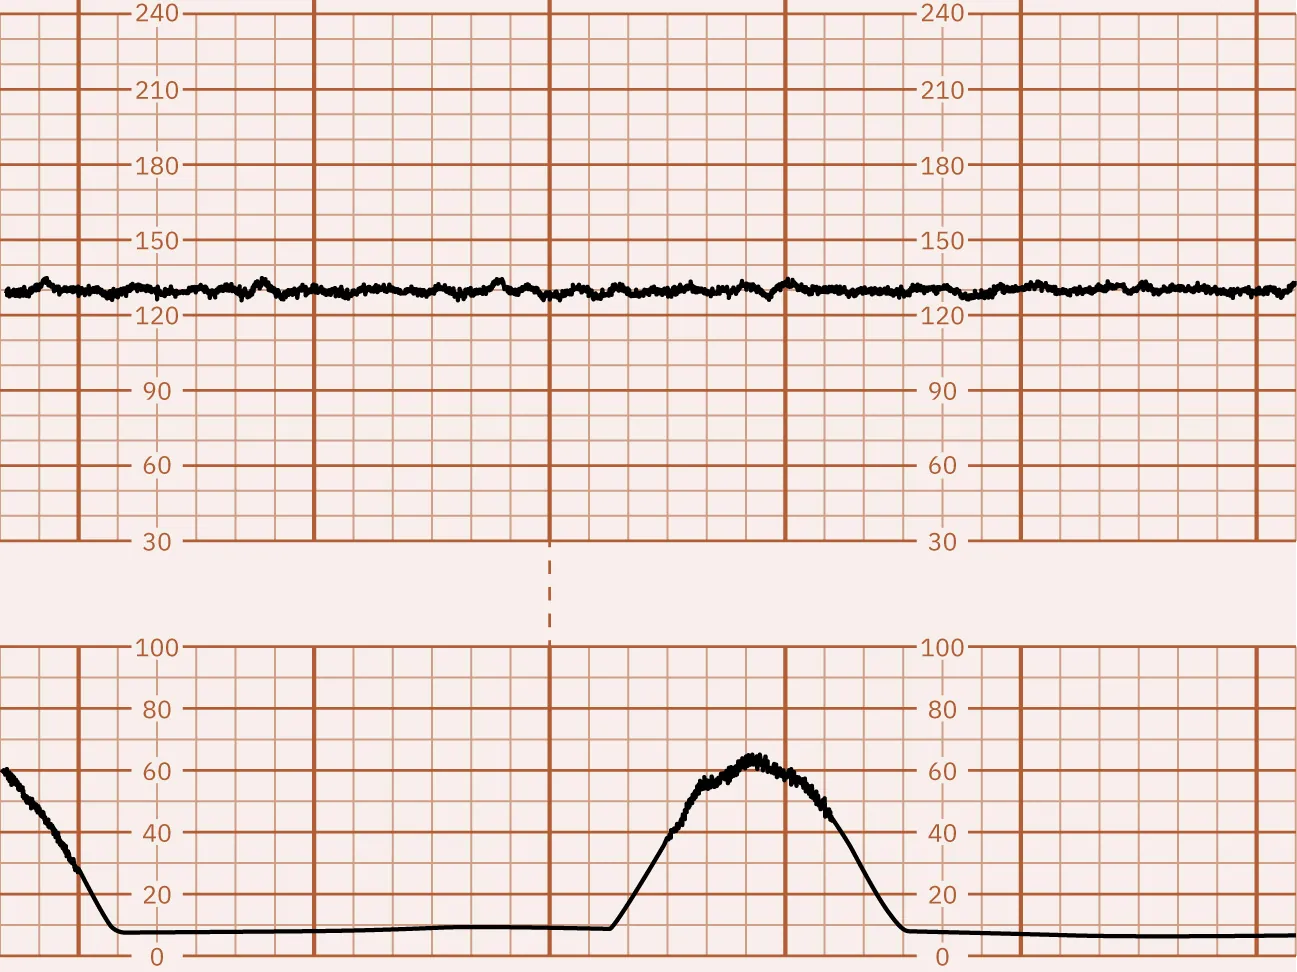

A lack of FHR baseline fluctuation is considered absent FHR variability. Absent variability is most often a sign of a severely compromised fetus. Figure 16.7 illustrates absent FHR variability. Fetal compromise can be the result of poor oxygenation leading to metabolic acidosis. Fetal acidemia depresses the CNS, causing a loss of FHR variability. Acidemia of the pregnant person can also cause absent FHR variability. Changes in the FHR variability from moderate to minimal or to absent may indicate fetal stress and require further investigation by the nurse and notification of the health-care provider.

Fetal heart rate reading indicating absent variability.

Figure 16.7 Monitor Tracing That Indicates Absent FHR Variability This monitor tracing shows absent FHR variability, essentially a straight line. (attribution: Copyright Rice University, OpenStax, under CC BY 4.0 license)